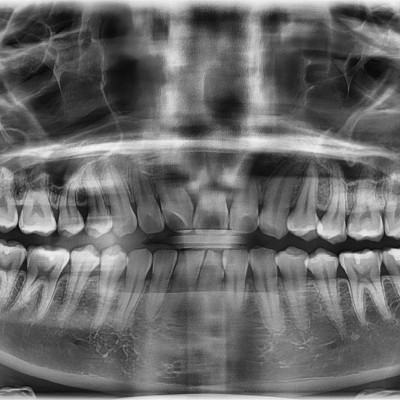

#18,28,38,48 사랑니 발치 #18,28,38,48 사랑니 발치 구강 외과 전문의가 당일 발치했습니다. ------------------..

작성자 이턱이 작성일 01-29 조회 4